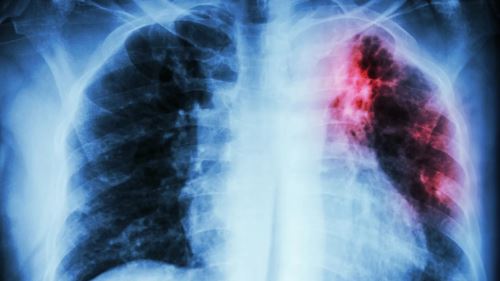

Walaupun dunia telah melangkah jauh dalam bidang perubatan moden, penyakit batuk kering atau tuberkulosis (Tibi) masih kekal sebagai pembunuh berjangkit utama dunia. Menurut laporan tahunan terbaharu Pertubuhan Kesihatan Sedunia (WHO), penyakit ini meragut kira-kira 1.23 juta nyawa pada tahun 2024 satu angka yang membuktikan ancaman Tibi masih belum berakhir.

Tibi disebabkan oleh bakteria Mycobacterium tuberculosis, yang biasanya menyerang paru-paru. Ia merebak melalui udara, apabila penghidap Tibi batuk, bersin atau meludah, bakteria halus boleh terbang di udara dan menjangkiti orang lain yang menghirupnya.